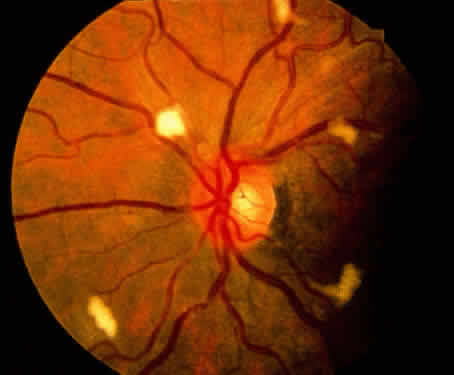

Retinal microvasculopathy occurs in more than 50% of HIV-infected patients (see Table 2). The most commonly observed manifestation is cotton-wool spots (Fig. 11), although intraretinal hemorrhages, microaneurysms,241,242 and, uncommonly, retinal ischemia12,243 also occur. With the exception of retinal ischemia, these findings are transient. All forms of retinal microvasculopathy increase in frequency in more advanced stages of HIV infection.241,242 Hypotheses regarding the pathogenesis of retinal microvasculopathy parallel those suggested for conjunctival vascular changes,149 and include HIVinduced increase in plasma viscosity, HIV-related immune complex deposition, and direct infection of the conjunctival vascular endothelium by HIV. HIV-associated retinal microvasculopathy is typically asymptomatic, but may play a role in the progressive optic nerve atrophy,244,245 electroretinographic abnormalities,246 and loss of color vision, contrast sensitivity, and visual field observed in HIV-infected patients.247,248 The role of retinal microvasculopathy in the development of CMV retinitis is controversial, with some investigators finding no relationship242 and others suggesting that retinal vascular damage may provide increased access to circulating CMV-infected lymphocytes.249

Fig. 11. Retinal microvasculopathy with numerous cotton-wool spots in a patient with AIDS.